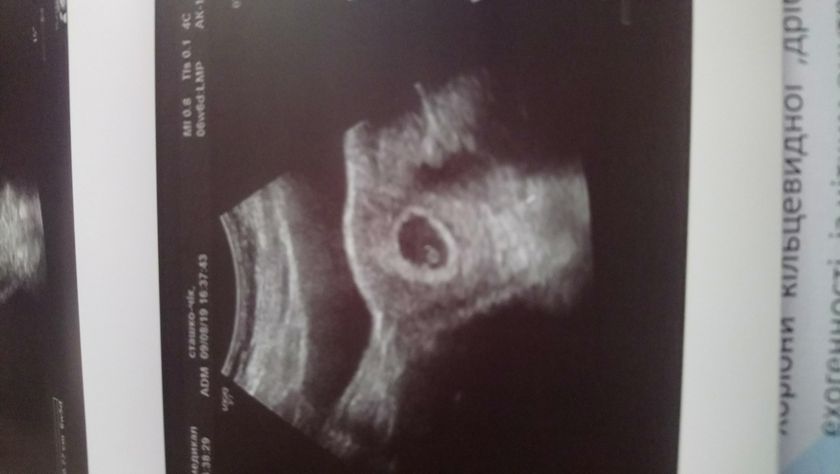

От мои размеры на 6 недель и 6 дней по изи(по месячным 7 недель) тоесть разница в один день.

ПЯ- 23мм

КТР- 7,7мм

ЖМ- 4 мм

СБ+

Гематом нет, угроз нет.

Заключение: прогресирующая беременность 7 недель.